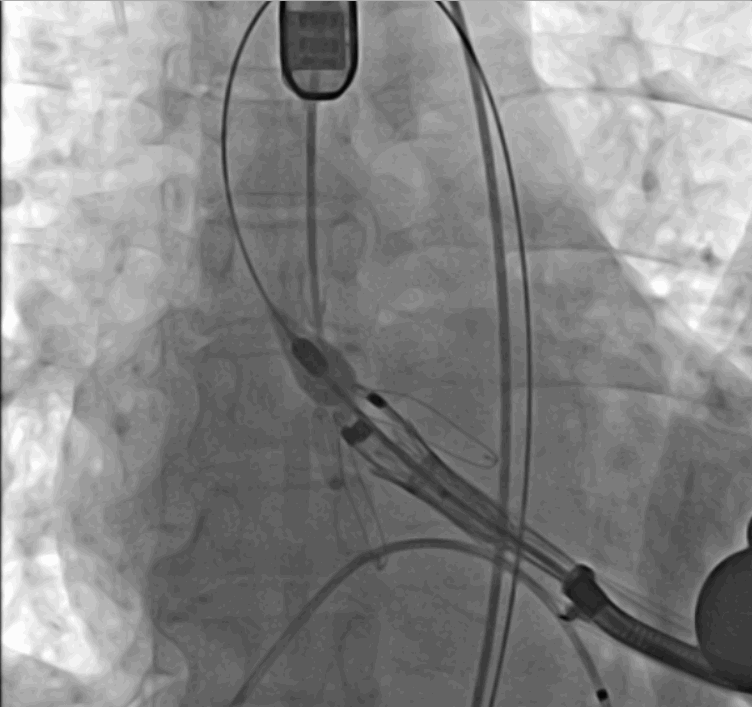

術中瓣膜釋放過程

手術采用經心尖入路,對患者進行全麻后,在左側心尖處做3-4cm微創手術切口,在DSA及超聲引導下手術順利完成。從導入器械到完成瓣膜置入,僅耗時約10分鐘。術后即刻主動脈瓣返流程度由術前大量返流轉為消失,患者于導管室拔除氣管插管,次日由ICU轉入普通病房。